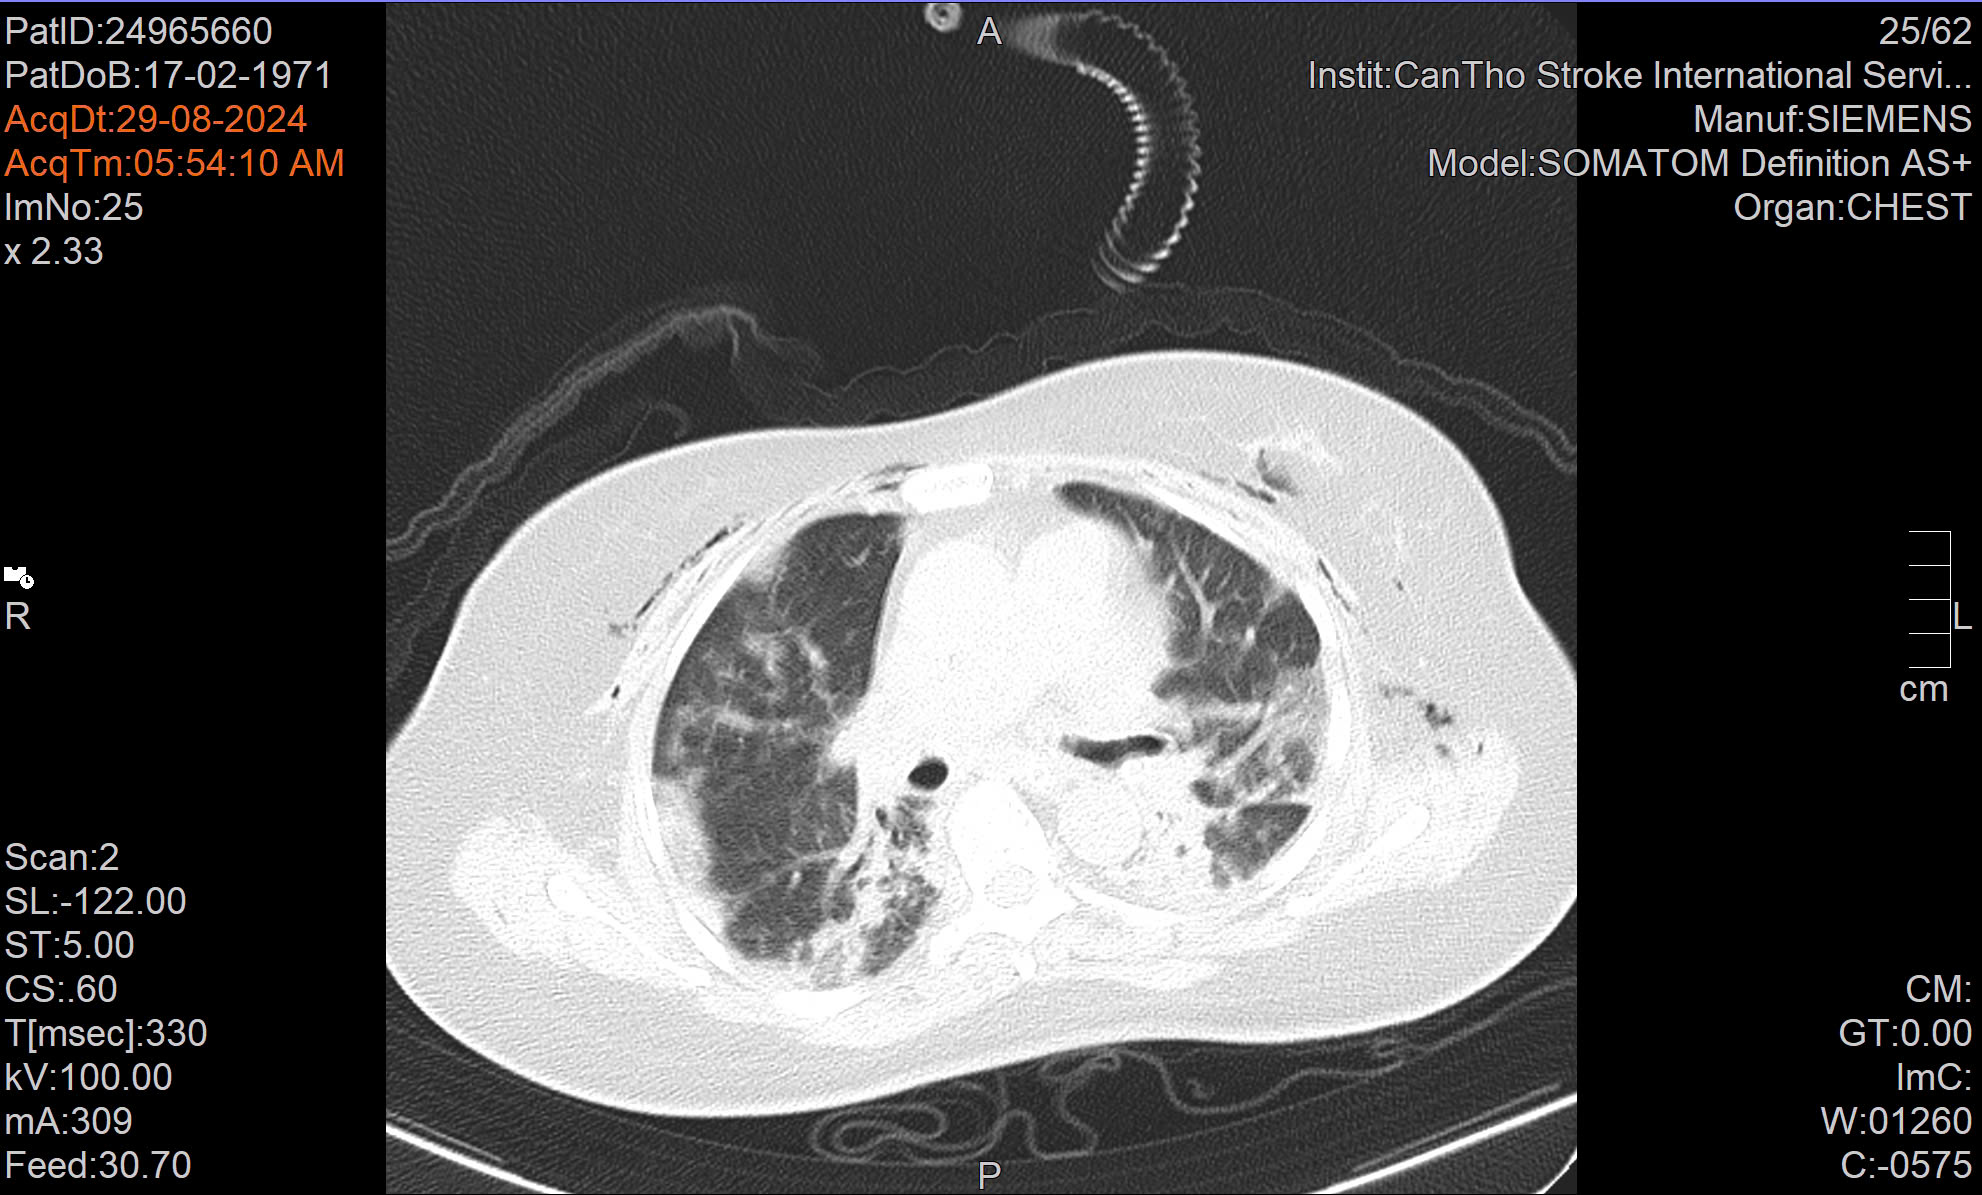

5 tiếng phẫu thuật can thiệp cứu sống bệnh nhân phình động mạch chủ bụng phức tạp, dọa vỡ

Mới đây, Bệnh viện Đa khoa S.I.S Cần Thơ đã kết hợp phẫu thuật và can thiệp nội mạch điều trị thành công cho người đàn ông 61 tuổi bị phình động mạch chủ bụng dưới thận, phình động mạch chậu, cứu sống người bệnh trong gang tấc trước nguy cơ biến chứng, tử vong.